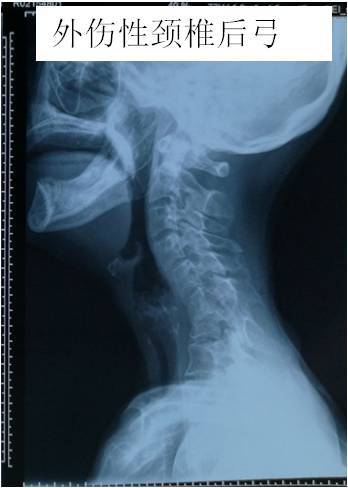

· 颈椎曲度反弓只是提示局部地方有退变,需要根据具体的症状做相应的处理。 如果是伴随颈部的地方疼痛和僵硬,可以选择按摩和热敷;另外就是可以选择药物比如替扎尼定,还可以选择一些膏药比如消痛贴膏有助于缓解。 如果是伴随上肢的麻木等不舒服,那么还可能是压迫了神经根,最好是完善颈部的磁共振检查,可以更为准确的判断病情。 平时要注意个人 · 知道颈椎反弓的成因,接着对因下药。 如果已经颈椎反弓了,可以适当地做一些牵引治疗。 如果病情较轻,通常采用坐位牵引,除此之外,还可以使用卧位牵引,可以在专业人士的指导下适当地借助一些工具,牵引的过程中,要注重牵引的强度,角度,时间以及重量。1510 · 颈椎反弓 一种常见颈椎病。颈椎有正常的生理弯曲,如果没有生理弯曲,甚至向相反的方向弯曲,称为反弓。 人类属于高级脊椎动物,颈椎"c"形向前的生理弧线保证了颈椎活动的高度灵活性,但人们常常发生违背颈椎生理曲线的姿态和活动。

1915 · 第一,颈椎反弓是一种普遍颈椎病。 颈椎骨有一切正常的生理弯曲,要是没有生理弯曲,乃至向反过来的方位弯折,称之为反弓。 颈椎反弓是组成颈椎病最常见的病理基本,而不适度用枕是造成 颈椎反弓的关键原因。 第二,颈椎反弓的严重后果: 颈椎反弓会造成许多 病症。 最先是颈椎骨主动脉受力,会造成大脑供血不足,次之是神经受力,造成神经根占位1 问: 颈椎反弓有什么后果,要怎么办 答: 颈椎反弓是会造成全身性的不正常的疾病。对人的危害极大。颈椎生理曲度变直或者颈椎生理曲反弓而造成颈椎管狭窄,挤压了脊髓而出现呕吐,眩晕,易昏撅摔倒而发生危险。脊髓病例一: 病情描述 颈椎曲度反弓如何解决颈椎曲度反弓如何解决 问题回答 病情分析:你好,预防颈椎病主要是减缓颈椎间盘退变的进程不良睡眠体位,工作姿势不当,不适当的体育锻炼都是颈椎骨关节退变的常见原因指导